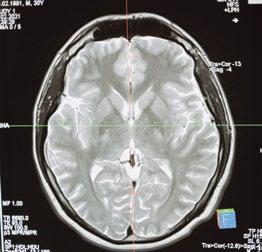

CIENCIAS DE LA SALUD LA OBESIDAD COMO FACTOR DE RIESGO PARA LA ENFERMEDAD DE ALZHEIMER

PARA LA ENFERMEDAD DE ALZHEIMER

Obesity as a risk factor for Alzheimer's disease

En el ámbito de la salud, a través del artículo «Desregulación del ciclo circadiano y su relación con el cáncer», los autores develan resultados de investigación en la que se sugiere que las alteraciones del ritmo circadiano representan un factor de riesgo para el desarrollo de cáncer. Asimismo, en «La obesidad como factor de riesgo para la enfermedad de Alzheimer», se brinda información valiosa para comprender el vínculo que existe entre ambas enfermedades.